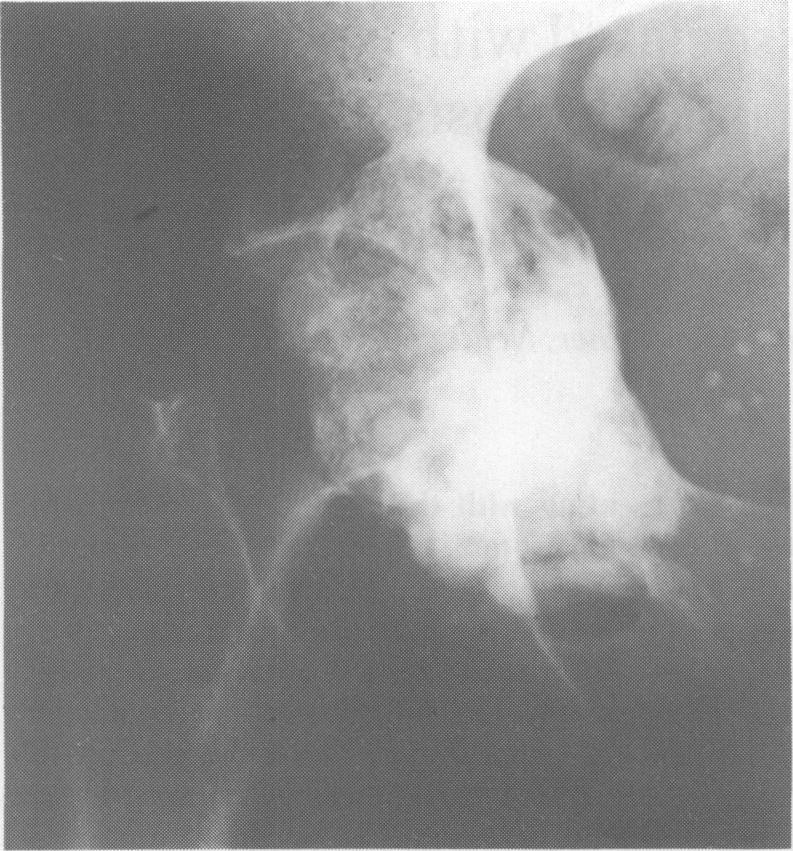

We describe a case of POEMS syndrome presenting with the recognized features of polyneuropathy, organomegaly, endocrine abnormalities, monoclonal protein, skin changes and anasarca. The patient was found to have both a solitary sclerotic plasmacytoma of the pelvis and evidence of Castleman's disease of lymph nodes. A number of unusual and unique features are also documented. Histological examination of affected skin demonstrated changes similar to urticaria pigmentosa including local oedema and mast cell infiltration. There was marked thrombocythaemia which has been seen in only one previous case and in addition the patient developed diffuse vascular calcification in the absence of recognized aetiological factors. Radiotherapy of the pelvic lesion and chemotherapy to control the myeloproliferative disorder gave rise to significant improvement in neuropathy. Control of anasarca required steroid therapy in addition to diuretics. The significance of these observations is discussed in relation to previous reports.

我们描述了一例POEMS综合征病例,其具有多发性神经病、器官肿大、内分泌异常、单克隆蛋白、皮肤改变和全身性水肿等公认特征。该患者被发现患有骨盆孤立性硬化性浆细胞瘤以及淋巴结Castleman病的证据。还记录了一些不寻常和独特的特征。对受累皮肤的组织学检查显示出类似于色素性荨麻疹的变化,包括局部水肿和肥大细胞浸润。存在明显的血小板增多症,此前仅在一例病例中见过,此外,患者在没有公认病因的情况下出现了弥漫性血管钙化。对骨盆病变进行放疗以及化疗以控制骨髓增殖性疾病,使神经病变有了显著改善。除利尿剂外,控制全身性水肿还需要类固醇治疗。结合先前的报告讨论了这些观察结果的意义。